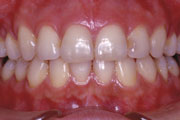

症例2:乱杭歯(叢生)